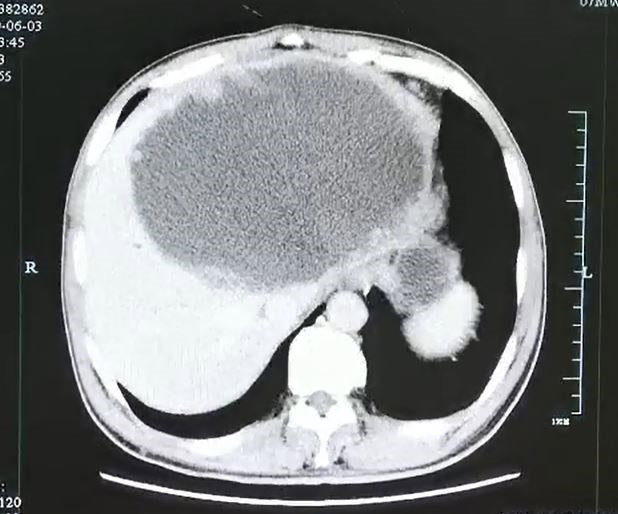

ภายหลังจากแพทย์ตรวจเช็กร่างกายอย่างละเอียด ก็พบว่า ตับของคนไข้มีถุงหนองขนาดใหญ่ ความยาว 7.5 นิ้ว และลึก 4.7 นิ้ว และสุดท้ายก็จำเป็นต้องตัดตับที่เสียหายของคนไข้ทิ้งไปถึงครึ่งหนึ่ง หลังจากพบว่ามีการติดเชื้อ และจากตรวจสอบในขั้นต่อมา ทำให้แพทย์ต่างตะลึงไม่น้อย เมื่อพบว่าภายในรูที่มีไข่จำนวนนับไม่ถ้วน เป็นของพยาธิใบไม้ตับ ซึ่งมีสาเหตุมาจากการกินอาหารที่ไม่ผ่านการปรุงสุก